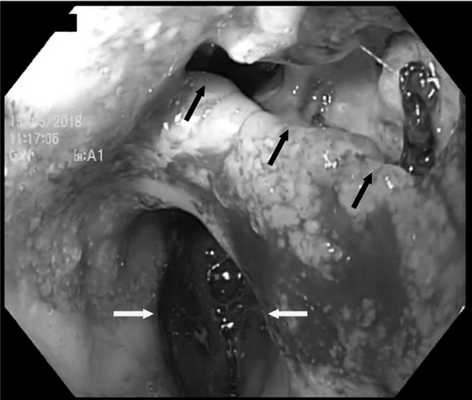

Помимо этого, для предварительной оценки зоны несостоятельности анастомоза, ее размеров и расположения всем пациентам выполнена ЭГДС (рис. 3). Рис. 3. Эндоскопическая картина у пациента после трансхиатальной эзофагэктомии с пластикой пищевода изоперистальтической желудочной трубкой. Желтыми стрелками указан просвет желудочной трубки, черными — зона несостоятельности анастомоза.